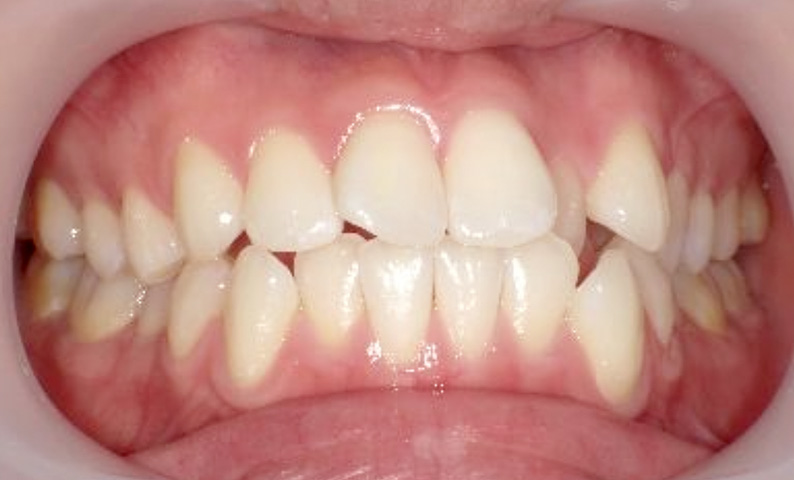

症例_025 上下顎の部分矯正

治療期間:13ヶ月金額:51万円+税女性前歯のガタガタ出っ歯

| Before | After |

|---|---|